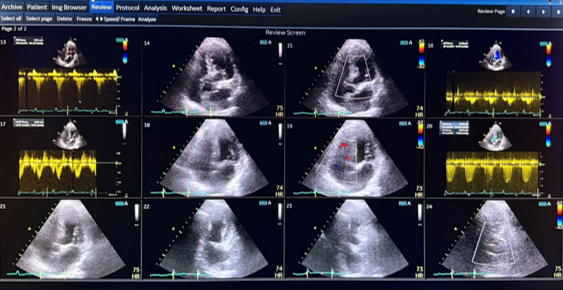

Echocardiogram (Cardiac Ultrasound)

Our trained staff performs echocardiography using advanced ultrasound technology.

“Real-time ultrasound image showing the heart chambers and valves.

The test usually takes 20 minutes. A small handheld device (transducer) is placed on the chest with gel to obtain images. There is no radiation, no needles, and the procedure is painless.